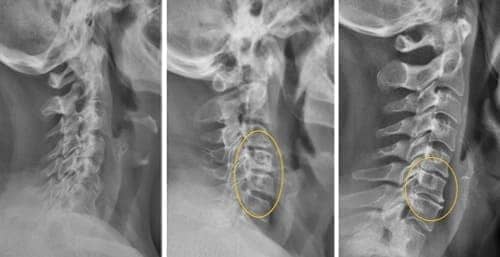

Погледнете този случай: това е гръбначният стълб на 44-годишен човек, който показва дегенеративни промени, характерни за напреднала възраст. Преди подобно разрушение се случваше след 60, а днес – още на 40. Тези промени напредват с възрастта и ако бъдат пренебрегнати, това означава риск от пълна загуба на подвижност!

Погледнете тези снимки – това е съдбата на тези, които не са реагирали навреме. Днес те са безпомощни и много от тях нямат никого, който да им помогне. Наистина ли искате такъв край?

- Всички тези снимки показват, че гелът „Reumax” възстановява здравето на ставите, дори в случаи, когато диагнозата изглеждаше като смълртна присъда. Без хирургични интервенции, без мъчителни болки, всички пациенти успяха да постигнат стабилно подобрение и да се върнат към нормалния си живот. ТОЗИ ГЕЛ НАПЪЛНО ПРОМЕНИ ХОДА НА ЛЕЧЕНИЕТО НА СТАВИТЕ И ГРЪБНАКА!